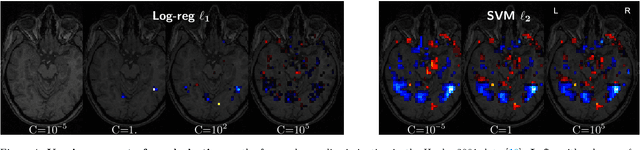

Abstract:Decoding, ie prediction from brain images or signals, calls for empirical evaluation of its predictive power. Such evaluation is achieved via cross-validation, a method also used to tune decoders' hyper-parameters. This paper is a review on cross-validation procedures for decoding in neuroimaging. It includes a didactic overview of the relevant theoretical considerations. Practical aspects are highlighted with an extensive empirical study of the common decoders in within-and across-subject predictions, on multiple datasets --anatomical and functional MRI and MEG-- and simulations. Theory and experiments outline that the popular " leave-one-out " strategy leads to unstable and biased estimates, and a repeated random splits method should be preferred. Experiments outline the large error bars of cross-validation in neuroimaging settings: typical confidence intervals of 10%. Nested cross-validation can tune decoders' parameters while avoiding circularity bias. However we find that it can be more favorable to use sane defaults, in particular for non-sparse decoders.